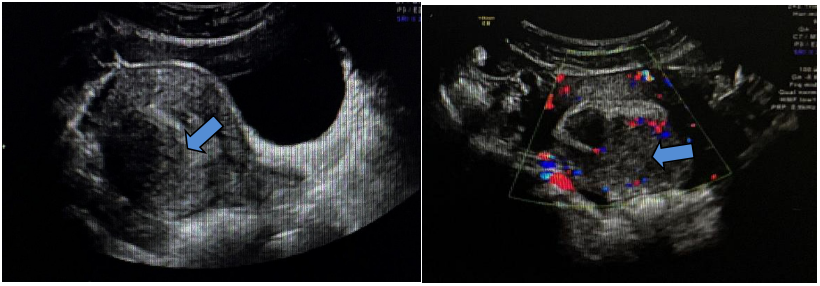

以“子宫肌瘤剔除术后14个月,子宫肌瘤复发11个月”再次返院就诊,盆腔增强磁共振成像(MRI)提示:子宫体大小约7.4 cm×6.8 cm×8.0 cm(含病变),子宫肌瘤大小约5.0 cm×4.8 cm×4.6 cm,突入宫腔,其内多发囊变,考虑子宫粘膜下肌瘤。

第二次手术后3个月,复查超声见子宫体大小约6.4 cm×6.5 cm×6.1 cm,子宫后壁肌层回声不均质,内见非均质回声,范围约5.2 cm×4.4 cm×3.9 cm,内见不规则暗区,较大范围约1.1 cm×1.1 cm×0.8 cm;CDFI内见点状血流信号,宫腔居中。考虑子宫肌瘤二次复发,因患者年轻、未生育,予GnRHa治疗3个月。

距离第二次手术后8个月,复查超声见子宫体大小约6.2 cm×9.6 cm×4.1 cm,肌层回声不均质,后壁可见囊实性回声,范围约8.6 cm×6.4 cm×4.8cm,略压向宫腔,内见不规则暗区,范围约分别为1.3 cm×1.2 cm×0.6 cm、1.2 cm×1.6 cm×0.4 cm;CDFI示周边及内部均可见条状血流信号,宫腔居中。

第二次手术后10个月,复查超声见子宫体大小约5.6 cm×6.6 cm×5.7 cm,肌层回声不均质,右后壁贴近宫腔并大部外突,非均质回声,范围约9.2 cm×7.6 cm×8.8 cm,内见暗区,大小约7.1 cm×5.5 cm×3.4 cm,内见细密点状回声;CDFI示非均质回声,周边可见条形血流信号,宫腔居中。肿瘤标志物CA125为236.5 U/ml。